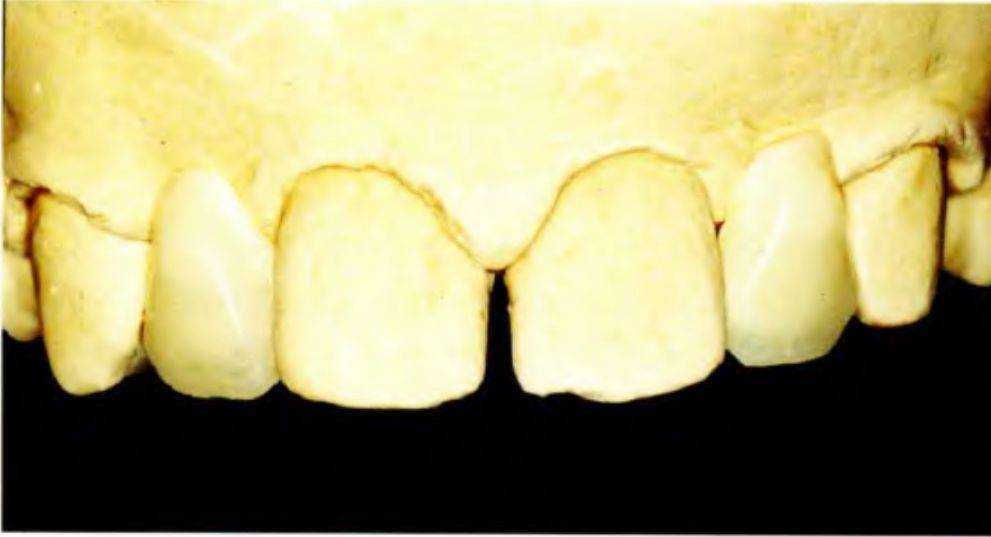

Рис. 5-За. Тринадцатилетний пациент с врожденным отсутствием боковых резцов верхней челюсти с помощью ортодонтических методов и последующее протезирование позволяют получить эстетически и функционально благоприятный долгосрочный результат. Таким образом достигается естественное положение клыков, оптимальное как с функциональной, так и с эстетической точки зрения. Только в нем они способны выполнять направляющую функцию при боковых и протрузионных движениях нижней челюсти. К передней группе зубов относится только медиальная часть клыка, дистальная часть относится к дистальной группе (рис. 5-2).

Ниже на примере клинического случая приведено поэтапное описание лечения пациента 13 лет с врожденным отсутствием верхних боковых резцов.

Планируется перемещение зубов латерально для создания пространства для установки имплантатов и последующего протезирования (рис. с 5-За по 5-Зе).